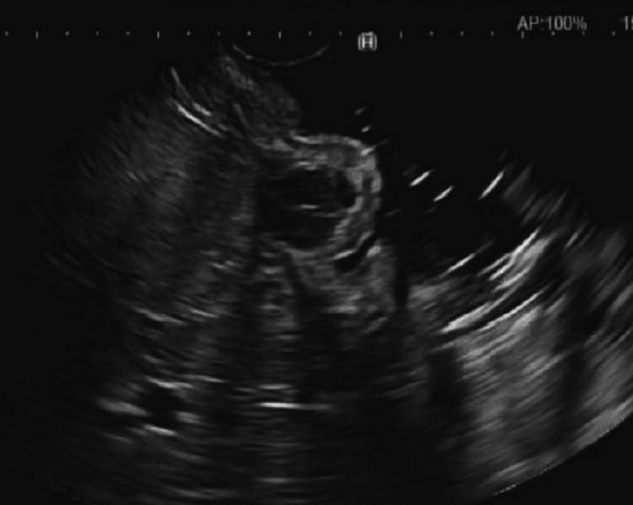

Figure 2.

EUS showing a 10-mm hypoechoic lesion arising from the muscularis propria.